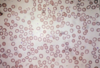

65yo male, increasing breathlessness on exertion, long history of diabetes mellitus and hypertension leading to poor renal function. Low Hb.

How would you best classify this patient’s anaemia?

What terms describe the red cell appearances?

What is the most likely reason for this patient’t anaemia?

Normocytic

Acanthocytes (burr cells), schistocytes (fragments), anisocytosis (diff shapes), poikilocytosis (diff sizes)

Erythropoietin deficiency. (Anaemia due to chronic renal failure and consequent EPO deficiency, anaemia usually normocytic with red cells showing abnormalities including spicules and “burr” cells. Red cell fragments may be seen with renal vascular disease).